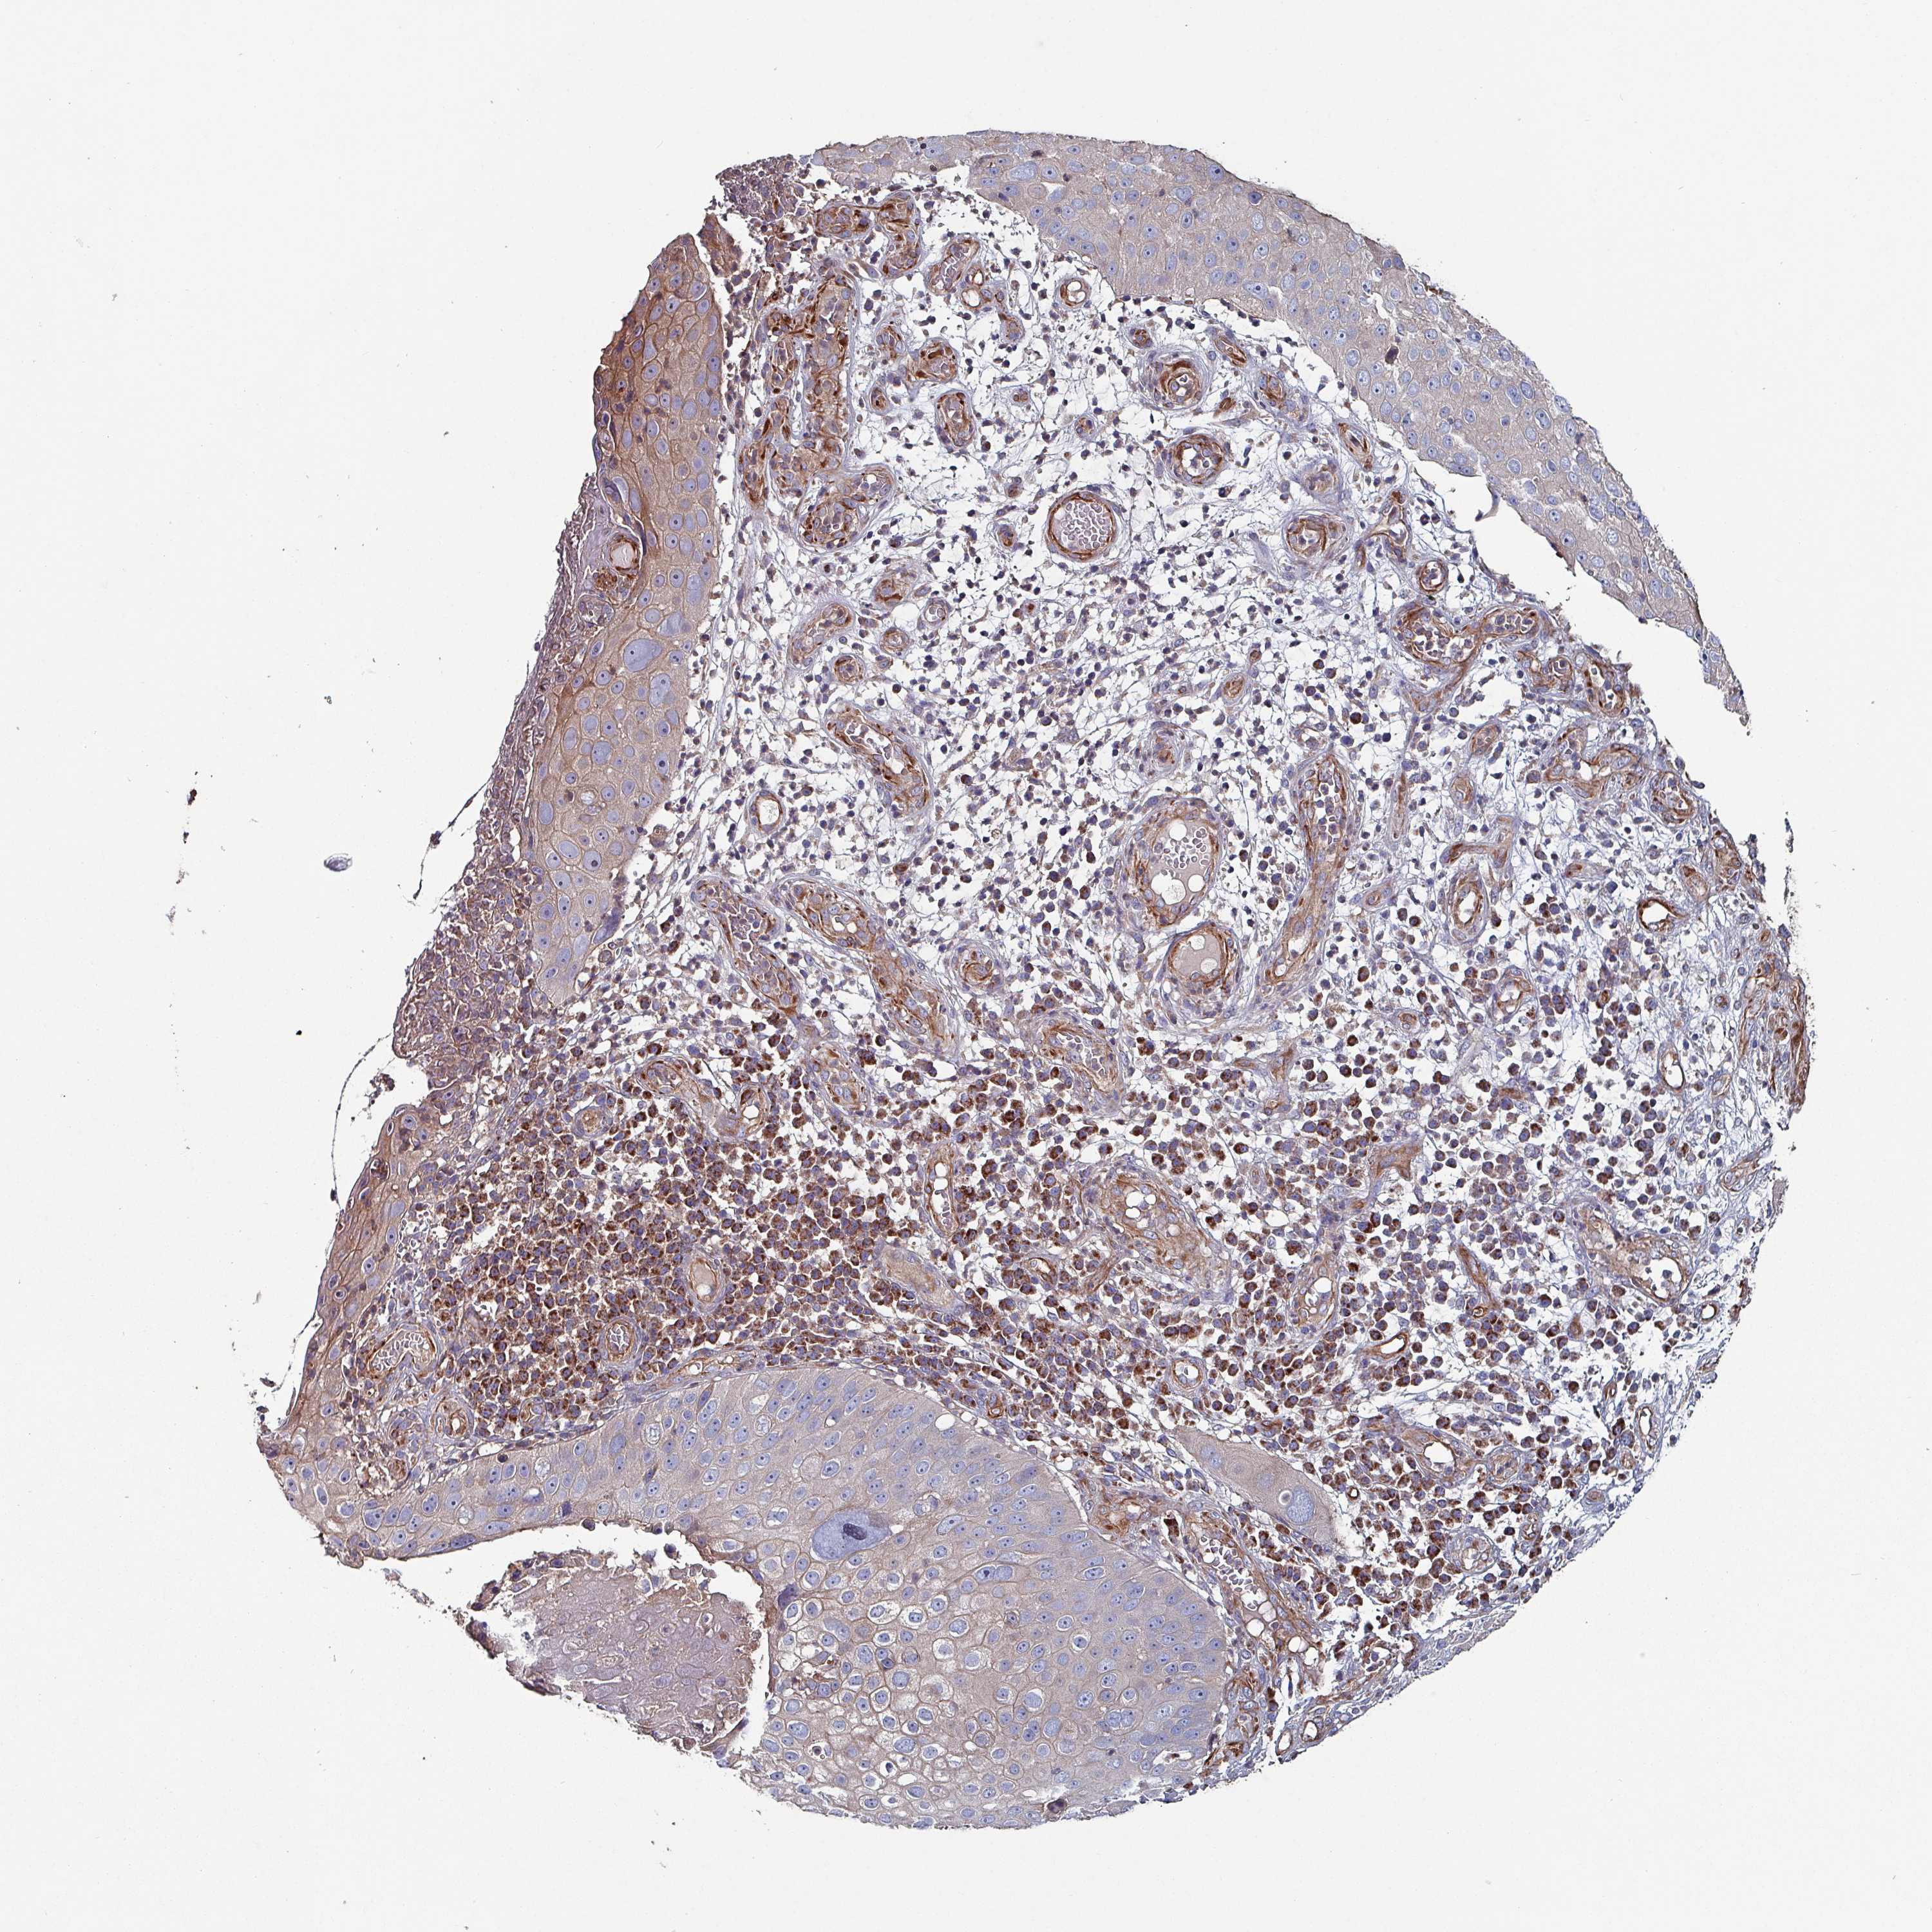

Basal cell and squamous cell cancer

SKIN CANCER - Protein expressioni

A mouse-over function shows sample information and annotation data. Click on an image to view it in a full screen mode. Samples can be filtered based on level of antibody staining by selecting one or several of the following categories: high, medium, low and not detected. The assay and annotation is described here.

Antibody stainingi

Antibody staining in the annotated cell types in the current human tissue is reported as not detected, low, medium, or high, based on conventional immunohistochemistry profiling in selected tissues. This score is based on the combination of the staining intensity and fraction of stained cells.

Each image is clickable and will lead to virtual microscopy that enables deeper exploration of all samples and also displays staining intensity scores, fraction scores and subcellular localization as well as patient and tissue information for each sample.

Antibody HPA051569

Staining

High

Medium

Low

Not detected

Intensity

Strong

Moderate

Weak

Negative

Quantity

>75%

75%-25%

<25%

None

Location

Nuclear

Cytoplasmic/membranous

Cytoplasmic/membranous,nuclear

Squamous cell carcinoma, NOS